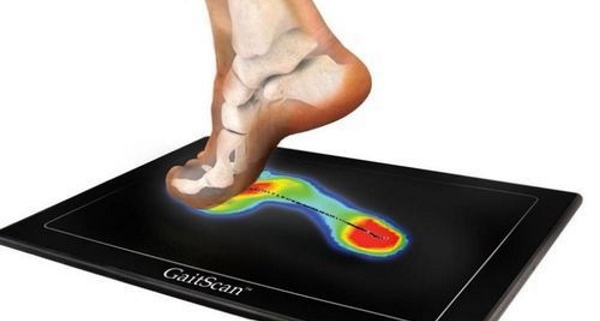

کلینیک سلامت پا پردیس با سابقه چندین ساله، به عنوان اولین مرکز تخصصی اسکن پا در این منطقه، به ارائه خدمات اسکن کامپیوتری پا و درمان غیرجراحی مشکلات مربوط به صافی کف پا، آرتروز زانو، انحراف زانوی ضربدری و پرانتزی، درمان خار پاشنه و میخچه، درمان درد ساق پا و کف پا، و درمان انحراف مفصل مچ پا مفتخر است.

این کلینیک با استفاده از جدیدترین و مدرنترین دستگاههای اسکنر پا با تکنولوژی از کشور آلمان، تمامی امکانات لازم برای تشخیص و درمان به روزترین روشها را فراهم میکند. تیم متخصصان کلینیک آمادهی خدمترسانی با استفاده از این تجهیزات مدرن است و همواره سعی میکند بهترین روشهای تشخیصی و درمانی را به بیماران ارائه دهد.

کلینیک سلامت پا در تهران و کرج، با سابقه چندین ساله و به عنوان اولین مرکز تخصصی اسکن پا مفتخر به ارائه خدمات اسکن کامپیوتری پا و درمان غیرجراحی در صافی کف پا، آرتروز زانو، انحراف زانوی ضربدری و پرانتزی، درمان خار پاشنه و میخچه، درمان درد ساق پا و کف پا، درمان انحراف مفصل مچ پا می باشد. این کلینیک مجهز به جدیدترین و مدرن ترین دستگاه های اسکنر پا با تکنولوژی کشور آلمان می باشد و آماده خدمت گزاری با استفاده از جدیدترین روش های تشخیصی و درمانی است.